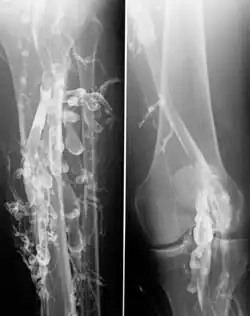

Trombóza cév dolních končetin

Angiografie se používá především k diagnostice cévních onemocnění, které můžeme rozdělit na nemoci tepen a nemoci žil: